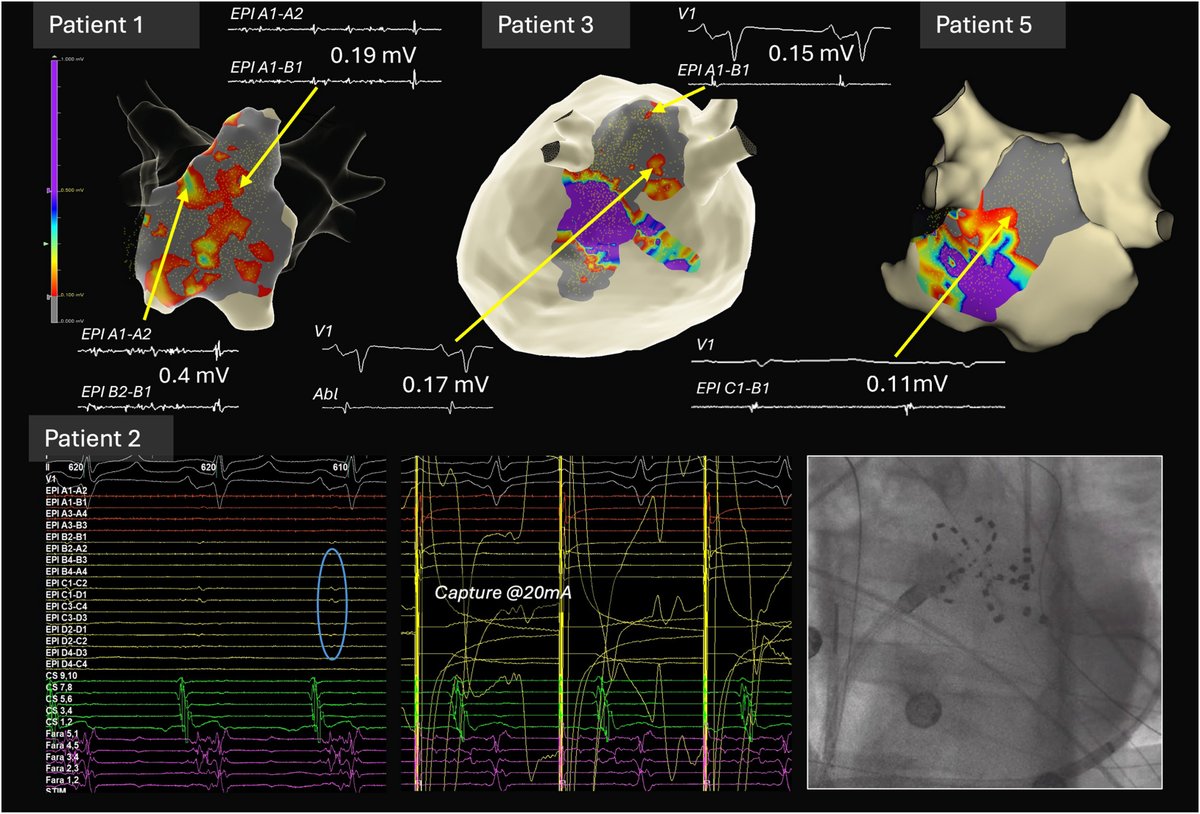

Anyone who has battled stubborn AF in HCM will benefit from reading this review we wrote with colleagues from multiple disciplines within the HCM community. @EthanRowin @MasriAhmadMD

Atrial Fibrillation in Hypertrophic Cardiomyopathy: A Unique Clinical Entity Requiring Dedicated Study #OpenAccess @EthanRowin @MasriAhmadMD heartrhythmjournal.com/article/S1547-…